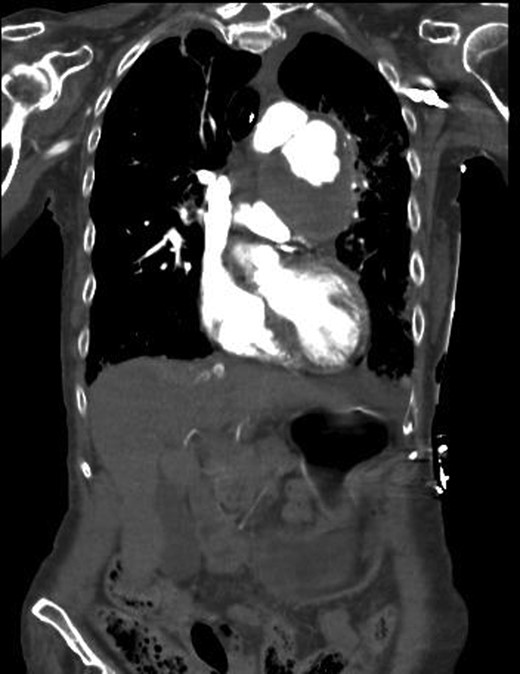

The CTA showed a large 7.3 × 6.8 cm haematoma in the left anterior mediastinum with active contrast extravasation from the left main pulmonary artery (Fig. 2). There was a moderate left-sided effusion but no aortic aneurysm or dissection seen.

CT chest showing a mediastinal haematoma with active contrast extravasation.